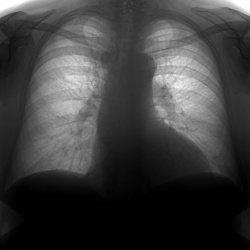

Здравствуйте. Цель исследования - исключить пневмонию. Отмечалось повышение температуры до 39, был контакт с больными, у которых пневмония была подтверждена. На мой взгляд, есть участок деформации...